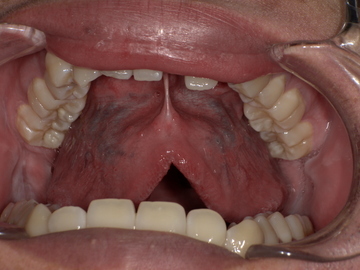

After

舌小帯形成術後、舌の動きがスムーズになり、上あごにしっかりと届くようになりました。これにより、発音に必要な舌の動きが改善されます。

成術を実施(約15分)

局所麻酔で痛みは最小限。術後は舌の動きが滑らかに。

● 術後経過

リハビリと発音練習を続けることで、約2週間後にはラ行・サ行の発音が明確になりました。

話すことへの自信を取り戻し、自然な会話ができるようになりました。